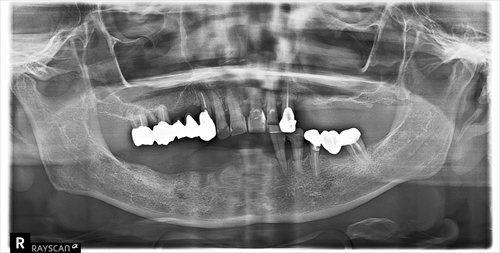

インプラントの本数が多数になる事、全身の問題があり、テレスコープデンチャーとなりました。

義歯を外したところです。歯に内冠と呼ばれるかぶせ物を装着し、その上に義歯をかぶせていきます。